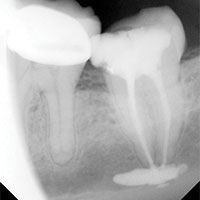

The Swiss procedure, developed in the 1950s, uses a paraformaldehyde paste in root canals. Some have embraced Angelo Sargenti as a savior to dentistry, claiming the procedure saves teeth and can be easily done by general dentists – not just licensed endodontists. But when the the Sargenti paste comes in contact with water, itturns to formaldehyde, an ingredient used in alming fluid.

“If the paraformaldehyde paste extrudes beyond the root tip, it will emit formaldehyde, which can erode the surrounding bone, destroy nearby connective tissues, and lead to numbness, paresthesias (feelings of pins and needles), jaw pain and infection of the maxillary sinus,” wrote Dr. Stephen Barrett in a piece entitled “Be Wary of Sargenti Root Canal Treatment” for Dental Watch.

Florida considers the Sargenti procedure to be “below the acceptable minimum standard of care” and disciplinary action can be taken if a dentist is found guilty of negligence by failing to meet state standards.

Routinely called Sargenti Paste or Sargenti Cement, the compound also is also known as N2, N2 Universal and RC2B. The Food and Drug Administration has banned interstate marketing of Sargenti-type materials. However, pharmacists can still lawfully prepare these types of pastes for local use in dentistry on a prescription-only basis.

Although a majority of Sargenti-type root canal procedures are performed without incident, there are other cases showing that when the procedure goes bad, it can go terribly bad and lead to chronic infection, multiple surgeries and loss of parts of the jaw and teeth.